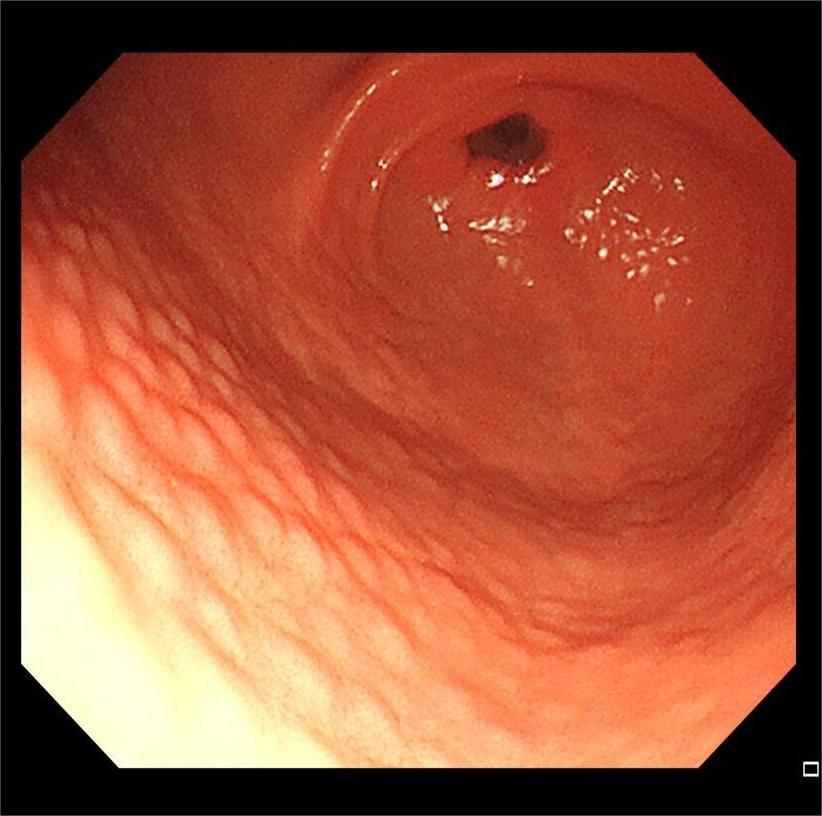

HPA感染鸡皮样胃炎